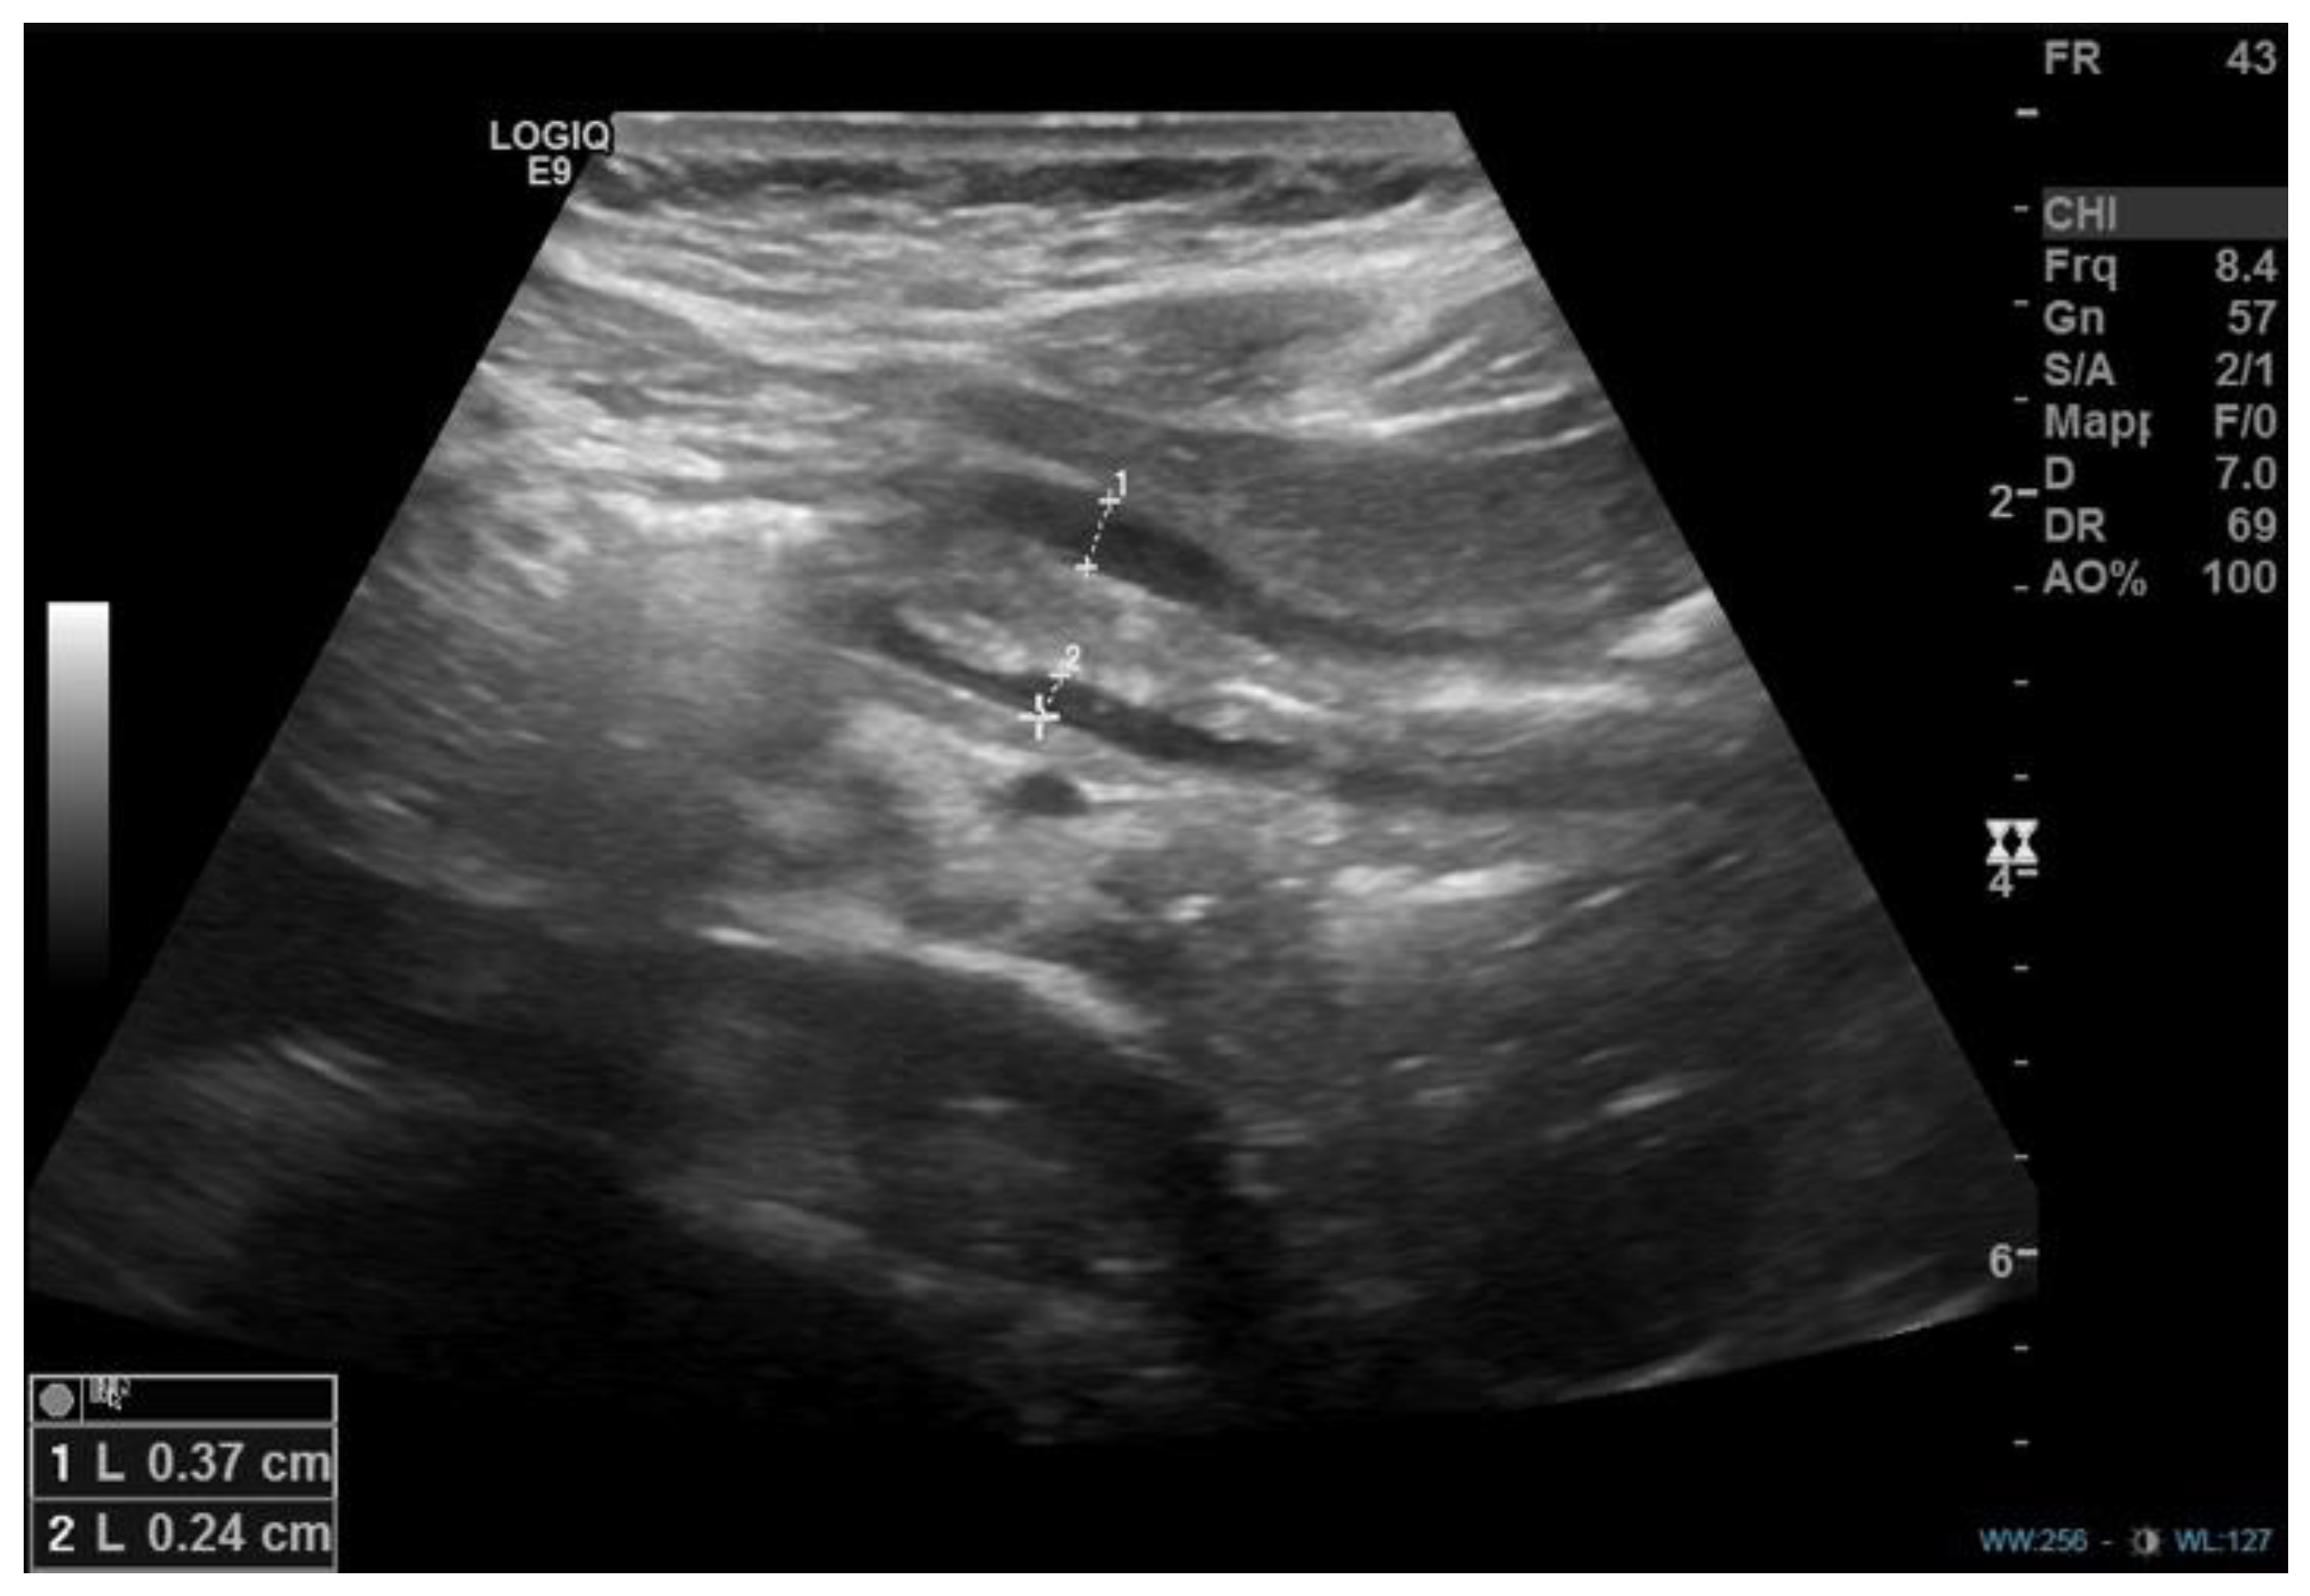

- Plessi, C.; Sica, M.; Molinaro, F.; Fusi, G.; Rossi, F.; Costantini, M.; Roviello, F.; Marano, L.; D’ignazio, A.; Spinelli, C.; et al. Diagnosis and treatment of primary hypertrophic pyloric stenosis (HPS) in older children. J. Pediatr. Surg. Case Rep. 2021, 69, 101860. [Google Scholar] [CrossRef]